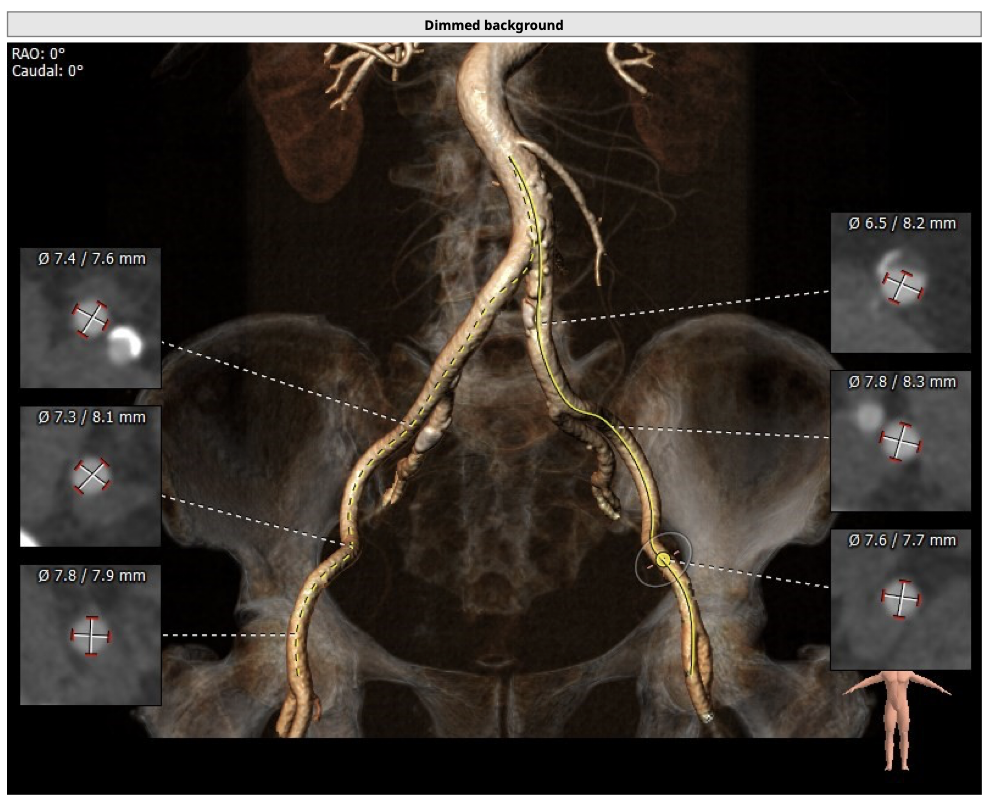

主动脉CT

难点分析:

*患者为四叶瓣,单纯返流,瓣膜锚定具有有一定难度,对释放瓣膜的把控要求高;

*右冠高度可,但左冠高度稍低,具有一定冠脉风险;

*心脏角度略大,释放瓣膜时,瓣膜与瓣环同轴性差。

制定策略:

经分析研判,拟从右侧股动脉穿刺入路,结合患者返流特点与主动脉根部结构,选用L26号的VenusA-Valve瓣膜,使用VenusA-Plus可回收输送系统,确保手术安全和瓣膜的稳定释放,必要时可使用圈套器辅助瓣膜释放,瓣膜释放后结合造影和超声情况,决定是否后扩。